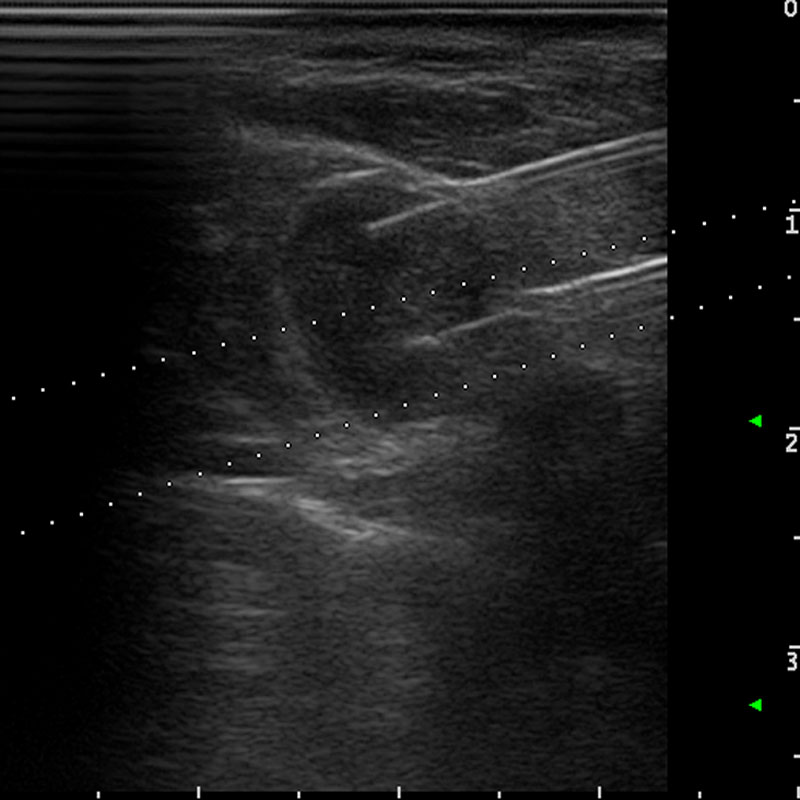

Modìlite consiste nell’inserimento di fibre ottiche (da 1 a 2 in funzione della dimensione del nodulo), per via percutanea, e nell’erogazione di energia laser per alcuni minuti che produce un riscaldamento del tessuto fino alla sua distruzione. Successivamente la progressiva riduzione del volume del nodulo tiroideo (riduzione del volume almeno >50% rispetto al volume basale ad 1 anno dal trattamento) indotta dai naturali meccanismi di rimozione dei tessuti necrotici del corpo umano determina la scomparsa dei sintomi compressivi e danni estetici del collo. La pianificazione del trattamento, l’inserimento degli aghi e il monitoraggio avvengono sotto guida ecografica.

Un paziente con un nodulo solido, isoecogeno, nel lobo tiroideo destro di 20 ml, è stato sottoposto a trattamento di Termoablazione con EchoLaser. Durante il trattamento, il paziente non ha riferito alcun disturbo.

Paziente con linfonodo metastatico del collo da carcinoma tiroideo papillare è stato sottoposto a trattamento di Termoablazione EchoLaser con due fibre.